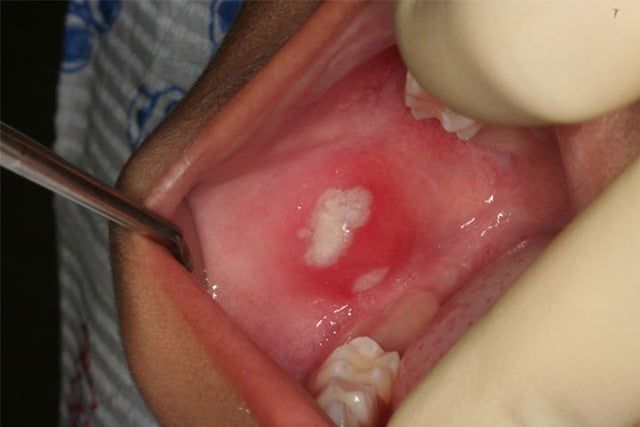

Traumatic Ulcer

It is not uncommon for children to inadvertently "bite" on their lips or cheeks, particularly following a dental visit where local anesthetic was used. The main reason why this occurs is the natural curiosity that a child has about the area of the mouth that is "numb." We try our best to explain to children that local anesthesia is temporary and we give them (and their parents) instructions on how to prevent "lip biting." In the event that this occurs, please notify our office so we can determine if your son or daughter will require treatment (i.e. antibiotics or pain medicine).